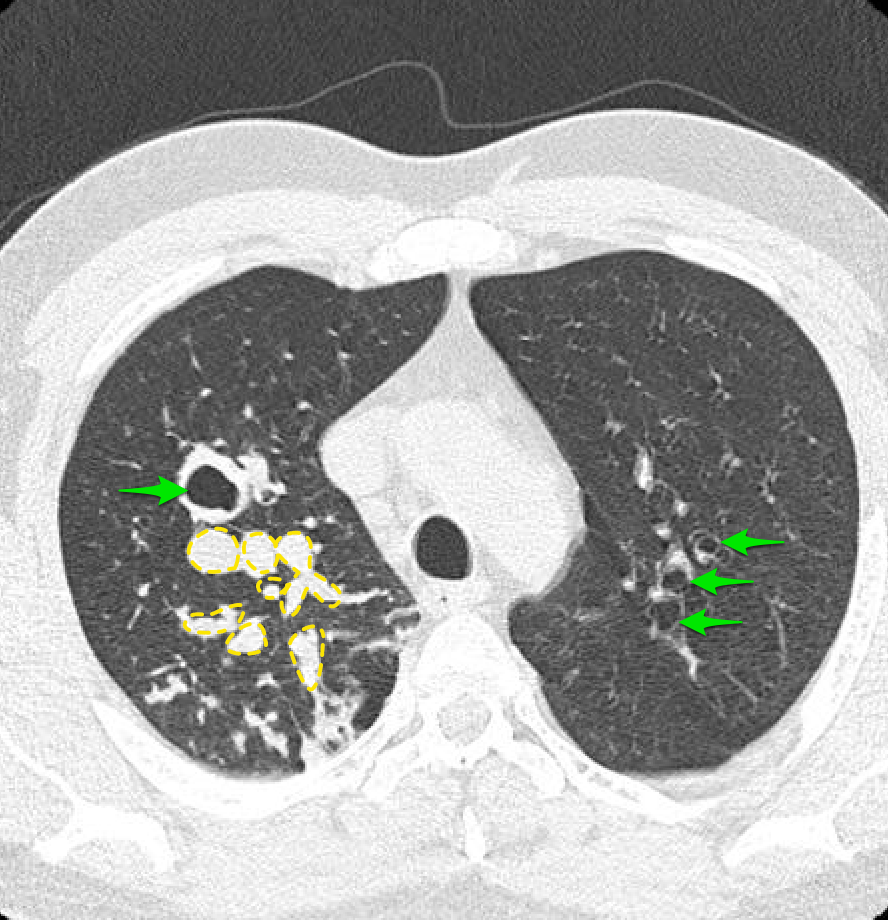

Фотографии и снимки КТ легких без контрастных веществ

Раздел: Визуальный дайджест